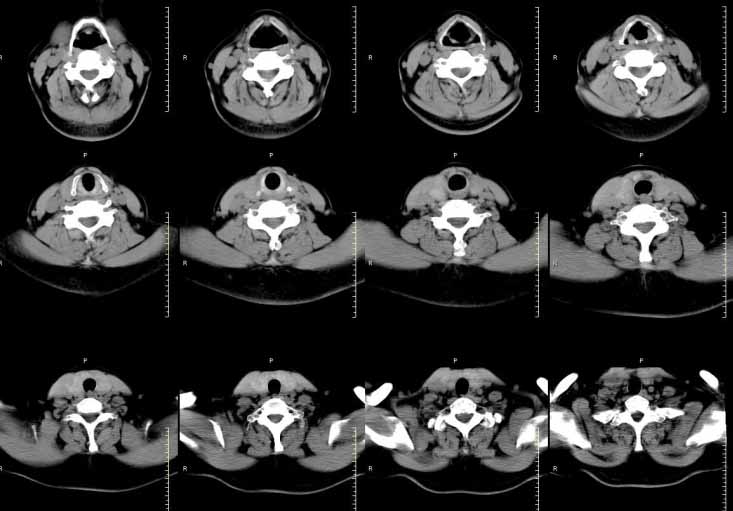

标题: CT22268:双侧甲状腺肿大

女,54岁,颈部增粗来就诊,体检示双侧甲状腺肿大,进行增强扫描,考虑为结节性甲状腺肿。

右侧见多个小的低密度影。图片太小,放大又不清楚。不好说。

看不太清楚,甲状腺左右叶弥漫性增大,密度不均匀减低,结甲及桥本氏甲状腺炎在ct上均可有此改变,需结合临床及实验室检查。